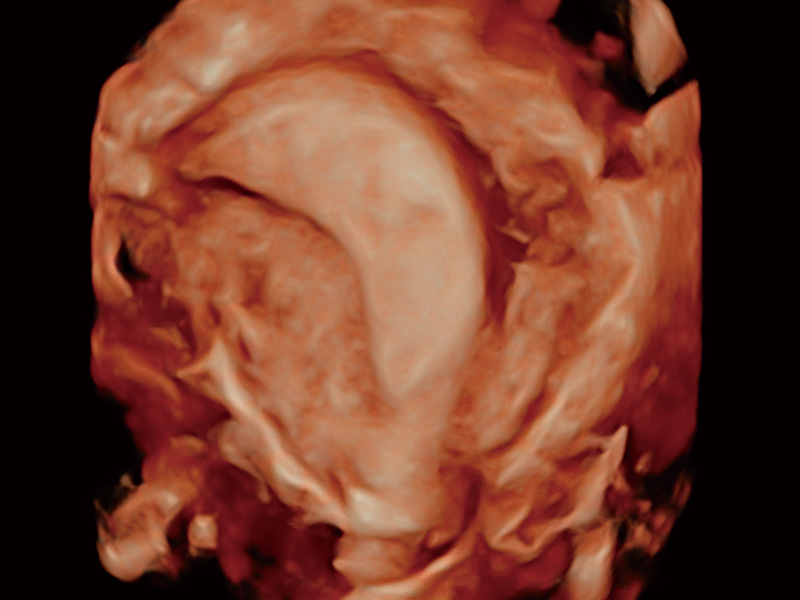

临床图

单角子宫